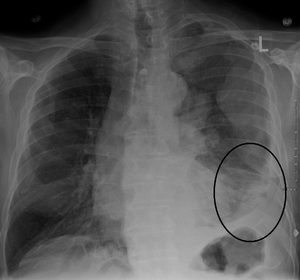

| CT scan showing a left sided mesothelioma with an enlarged mediastinal lymph node | |

More than 80% of mesothelioma cases are caused by exposure to asbestos.[3] The greater the exposure, the greater the risk.[3] As of 2013, about 125 million people worldwide have been exposed to asbestos at work.[13] High rates of disease occur in people who mine asbestos, produce products from asbestos, work with asbestos products, live with asbestos workers, or work in buildings containing asbestos.[3] Asbestos exposure and the onset of cancer are generally separated by about 40 years.[3] Washing the clothing of someone who worked with asbestos also increases the risk.[13] Other risk factors include genetics and infection with the simian virus 40.[3] The diagnosis may be suspected based on chest X-ray and CT scan findings, and is confirmed by either examining fluid produced by the cancer or by a tissue biopsy of the cancer.[2]

Imaging

Diagnosing mesothelioma is often difficult because the symptoms are similar to those of a number of other conditions. Diagnosis begins with a review of the patient's medical history. A history of exposure to asbestos may increase clinical suspicion for mesothelioma. A physical examination is performed, followed by chest X-ray and often lung function tests. The X-ray may reveal pleural thickening commonly seen after asbestos exposure and increases suspicion of mesothelioma.[15] A CT (or CAT) scan or an MRI is usually performed. If a large amount of fluid is present, abnormal cells may be detected by cytopathology if this fluid is aspirated with a syringe.[11] For pleural fluid, this is done by thoracentesis or tube thoracostomy (chest tube); for ascites, with paracentesis or ascitic drain; and for pericardial effusion with pericardiocentesis. While absence of malignant cells on cytology does not completely exclude mesothelioma, it makes it much more unlikely, especially if an alternative diagnosis can be made (e.g., tuberculosis, heart failure).[citation needed] However, with primary pericardial mesothelioma, pericardial fluid may not contain malignant cells and a tissue biopsy is more useful in diagnosis.[11] Using conventional cytology diagnosis of malignant mesothelioma is difficult, but immunohistochemistry has greatly enhanced the accuracy of cytology.[citation needed]